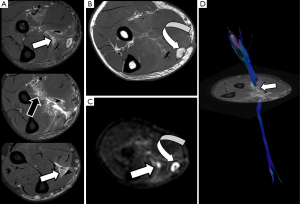

A different approach for the study and representation of PN is the use of DTI, a technique that has been widely used for the assessment of CNS, and in recent years, also in spinal cord (13-15). As discussed above, PN are highly anisotropic structures, presenting a facilitated diffusion along its longitudinal axis and a marked restriction of the free movement of water in the transverse plane. In order to characterize and quantify the water movement within nerves, it is necessary to acquire at least six diffusion directions with a maximum b value ranging from 800 to 1,200 s/mm2. The dominant direction is given by the principal eigenvector, and the other two perpendicular directions by two secondary eigenvectors (16). With these eigenvectors, which are the directional expression of a certain eigenvalues, several parameters can be calculated (Figure 2). Fractional anisotropy (FA) is the commonest used by radiologists. Other derived parameters from DTI are mean diffusivity (MD), axial diffusivity (AD) and radial diffusivity (RD), each one of those reflects a different property of the PN as it will be described below, and can be used as biomarkers of PN damage or regeneration (17).

After PN trauma there is an increase of the water content at the extracellular space and a disruption of the collagen structure support. In this scenario, DWN may demonstrate thickening and focal increase of signal intensity of PN at higher b values compared with normal PN (Figure 4). ADC parametric maps demonstrate increase of ADC values reflecting the increase of water movement within the extracellular space at the site of nerve damage (36). In a similar manner, an increase of MD values will be found at the injured nerve segment. However, these parameters may appear insufficient for an adequate nerve evaluation and may not show statistically significant differences between each nerve segments. Thanks to the development of DTN sequences, diverse studies have demonstrated a decrease of FA values, due to the loss of fiber anisotropy and the presence of edema (37). At the same nerve segment, an increase of RD is depicted due to the existence of a facilitated diffusion within the perpendicular plane owing to the disruption of physiological barriers that impeded the motion of water molecules in the short PN axis, mainly myelin sheaths but also endoneurium and perineurium (38) (Figure 5). This decrease of FA values and increase of RD values becomes more conspicuous at the compression site or traction/transection point, as well as in the distal segment, probably due to a Wallerian degeneration mechanism (39). These changes are less evident at proximal segments of the damaged nerve (37). Respecting AD, it might theoretically decrease at the distal segment of a damaged PN as there is interruption of the normal axonal flow (27). However, further studies are needed to confirm or reject this assumption (Figure 6).

Derived parameters from DWN or DTN, such as ADC or FA, have proved its usefulness to identify the involved lumbar nerve roots in cases of lumbar pain (57,58). An increase in ADC and a significant decrease in FA of compressed nerve roots compared with contralateral ones are detected in cases of symptomatic lumbar disk disease. This increase of ADC values is secondary to the venous congestion and edema that occurs in both pre-ganglionic and ganglionic segments of nerve lumbar roots (41). The decrease of FA values is also related to a loss of fiber anisotropy (Figure 11). At this point, it is important to remember that normal preganglionic nerve roots usually show physiologically lower FA values than PN, probably due to the absence of a complete neural fiber structure. This data has to be taken into account when quantification is performed at this small nerve structure, avoiding false positive results in patients without nerve compression. This quantitative assessment shows potential to form part shortly of the clinical lumbar spine MRI protocols as a tool to detect functional changes within the lumbar roots in patients with symptoms but without obvious disc protrusions (41).